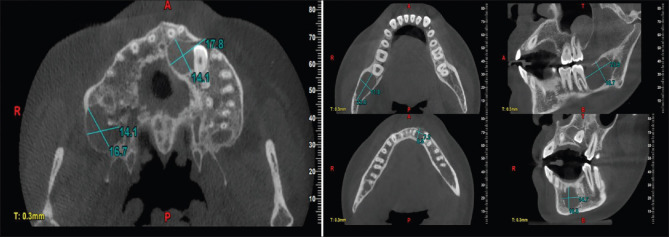

Rationale: The importance of a comprehensive and interdisciplinary approach in early diagnosis and managing patients with rare genetic disorders must be highlighted appropriately. This case report delves into the complex clinical presentation of a patient with Gorlin-Goltz Syndrome, emphasizing the multifaceted challenges encountered during diagnosis, treatment, and long-term management and involves a detailed exploration of the patient's clinical history, encompassing cutaneous manifestations, skeletal anomalies, and neurological findings radiological imaging also plays a pivotal role in guiding towards the diagnostic process and forming the basis for a multidisciplinary approach for management of the patient.

Patient concerns: A previously treated case for pain in lower left tooth region, patient concerns for pain and pus discharge from same region.

Diagnosis: After thorough clinical and radiographic findings patient was diagnosed with Gorlin goltz syndrome having multiple cysts.